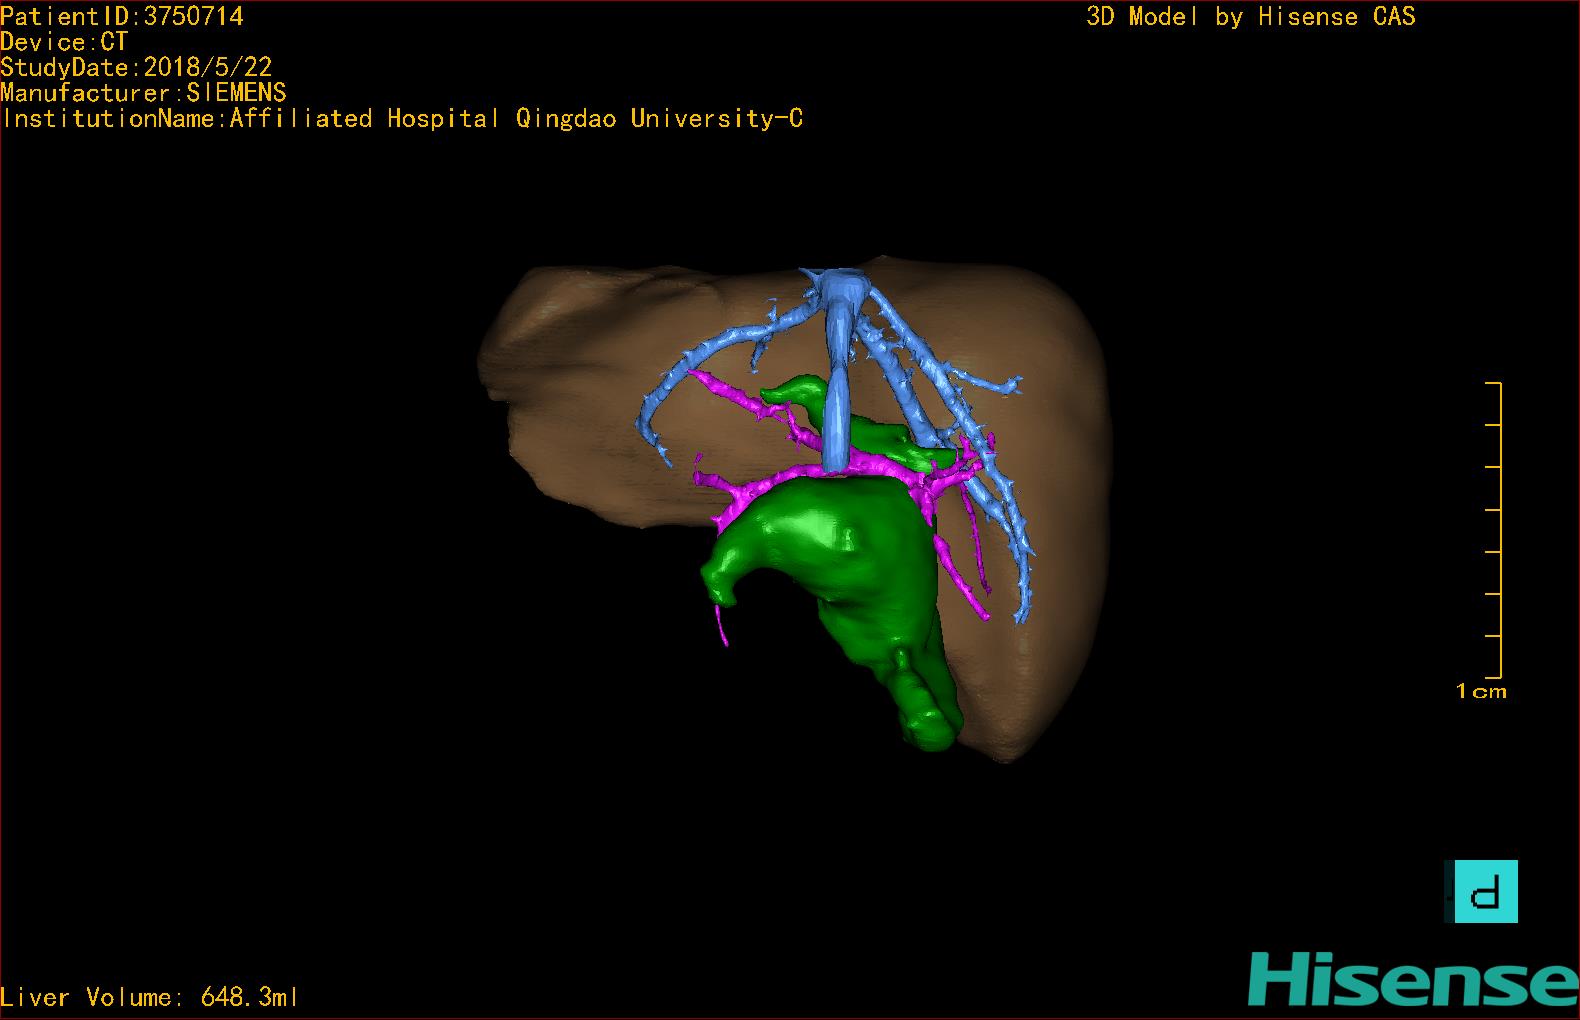

实验室检查: 血常规:WBC 16.16*109/L,NEU2.88*109/L,RBC3.76 1012/L,HB 92g/L, PLT 414*109/L 生化全套:ALT 50.00 U/L, AST 147.00 U/L, ALT/AST 0.34,LDH 367.00 U/L, ALB 36.91g/L, GGT 1297.00 U/L, ALP 1155.00 U/L, BIL-T 138.23 umol/L, BIT-D 97.01 umol/L, TBA 48.40umol/L,ADA 40.00U/L, PAB 121.40mg/L, BUN 1.98 mmol/L, CREA 17.00 umol/L 肝炎全套: 炎症反应标志物:CRP 7.27mg/l 诊疗过程: CT结果输入海信CAS系统后行3D重建及手术规划后,于2018-5-31全麻下行“胆总管囊肿切除+肝总管空肠吻合术”手术治疗: 术前三维重建及手术方案设计: 将0.625mm双源薄层CT资料的静脉期和动脉期Dicom格式文件导入海信CAS系统。 通过调节窗宽窗位调整CT序号,对肝实质,胆囊,下腔静脉,肿瘤,肝动脉、门静脉及肝静脉等进行三维重建;系统自动计算肝脏体积,肝脏体积为648.3ml,通过术前模拟手术,精准判断手术切除范围,进行精密术前规划及讨论后实施手术。 手术步骤: 麻醉成功后,患儿取平卧位,2.5%碘伏消毒手术区皮肤,铺无菌巾单。取右上腹纵口长约5m,切开皮肤、皮下织组,腹直肌前鞘、腹直肌,后鞘和腹膜。探查见:胆总管3×2cm大小,胆囊管迂曲,长约10cm。 剥离、切除胆囊,游离胆总管,将之横断:①近端即肝总管,剪裁后被吻合用;②远端游离切除囊肿内壁,直至胆总管开口于十二指肠处,冲洗后予以结扎缝扎。距treits韧带20cm处横断空肠:①近端与其远端25cm处的空肠侧壁行端侧双层吻合,吻合口通畅;②远端断端封闭,其侧壁剪开,并经横结肠后提至肝门处,与剪裁的肝总管行端侧双层吻合。缝合修补胆囊床及系膜裂孔,肝门部放置橡胶引流管一根。温盐水冲洗腹腔。检查无活动性出血,清点纱布器械无误,依次缝合腹壁各层。手术顺利,麻醉满意,出血不多,未输血,术后病人先进入麻醉恢复室,苏醒后回病房。手术时术者可开启Hisense CAS系统手势控制功能,对肝脏及胆囊解剖结构进行实时、全方观察、评估,起到术中导航作用。 术后病理: 1. (囊肿壁)囊肿性病变,囊壁部分区域衬覆柱状上皮。 2. 慢性胆囊炎。 3. 送检(肝门)淋巴结查见淋巴结1枚,呈反应性增生。 随访情况: 患儿术后2周恢复良好 术前CT检查:动脉期

术前三维重建:重建图片.jpg)

.jpg)